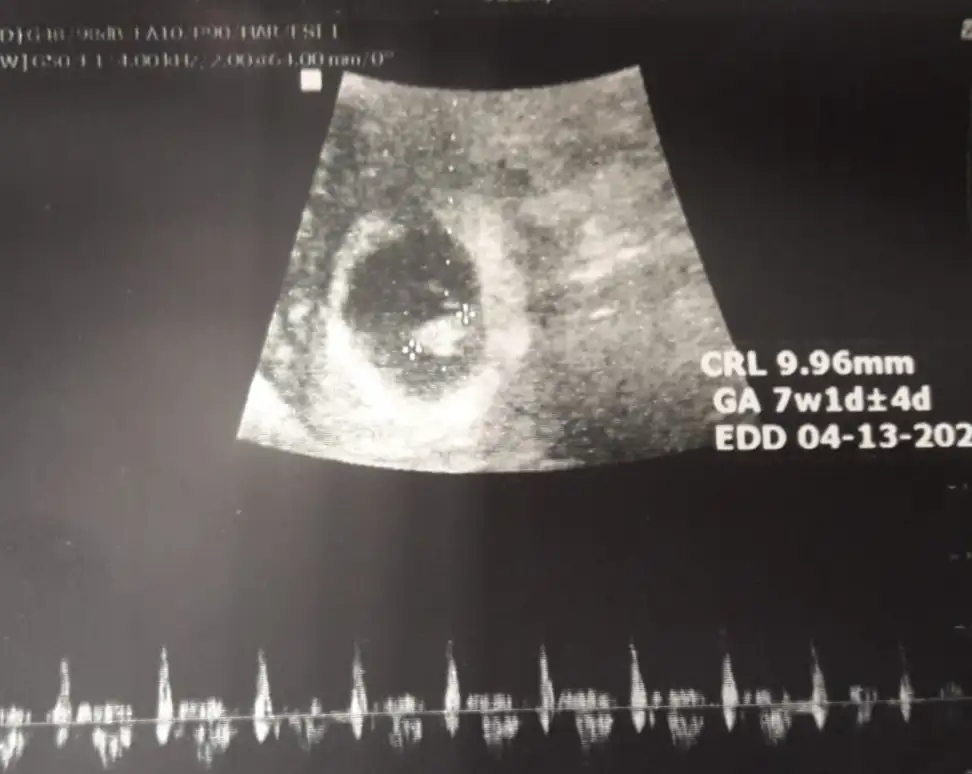

Buna göre kızEki Görüntüle 2309620 Bana da yorum yapar mısınız acabavajinal ultrason

6 yada 7 hafta olmalı

Saga yakın kız vajinalsa erkek